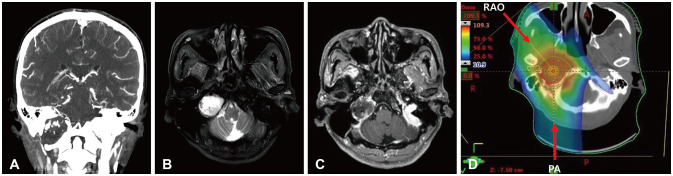

- Delayed cerebral necrosis is a well-known complication of radiation therapy (RT). Because of its irreversible nature, it should be avoided if possible, but avoidance occurs at the expense of potentially compromised tumor control, despite the use of the modern advanced technique of conformal RT that minimizes radiation to normal brain tissue. Risk factors for radiation-induced cerebral necrosis include a higher dose per fraction, larger treatment volume, higher cumulative dose, and shorter time interval (for re-irradiation). The same principle can be applied to proton beam therapy (PBT) to avoid delayed cerebral necrosis. However, conversion of PBT radiation energy into conventional RT is still short of clinical support, compared to conventional RT. Herein, we describe two patients with excessively delayed cerebral necrosis after PBT, in whom follow-up MRI showed no RT-induced changes prior to 3 years after treatment. One patient developed radiation necrosis at 4 years after PBT to the resection cavity of an astroblastoma, and the other developed brainstem necrosis that became symptomatic 6 months after its first appearance on the 3-year follow-up brain MRI. We also discuss possible differences between radiation changes after PBT versus conventional RT.